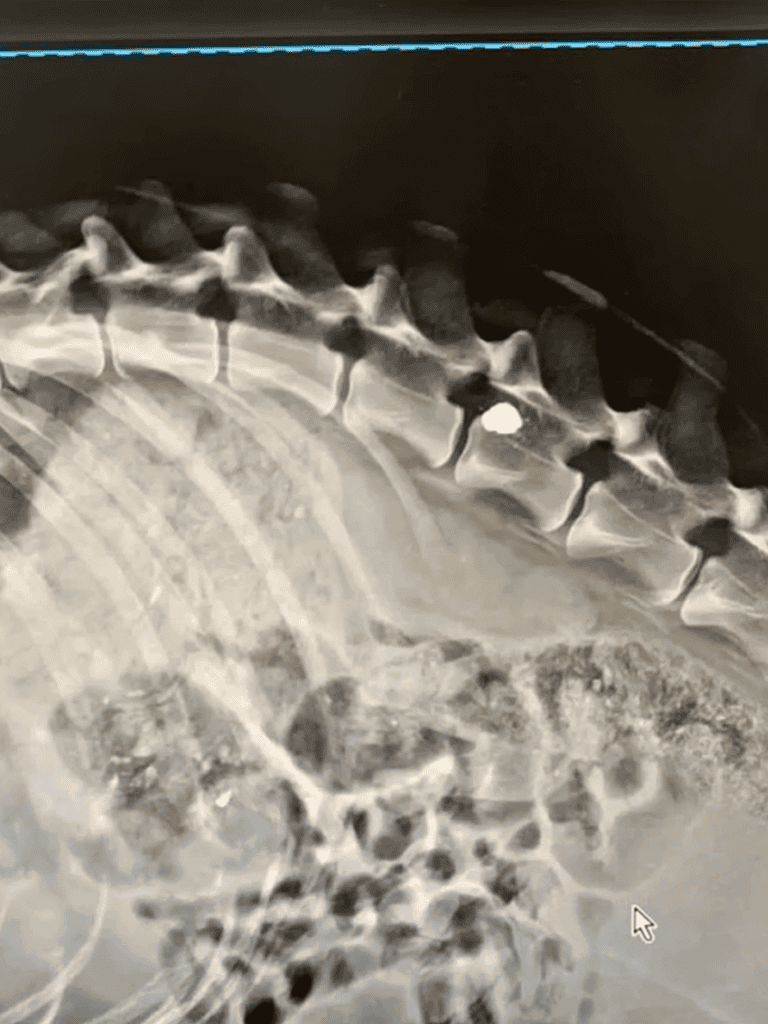

Alex was a brave dog facing a dire situation—a bullet was lodged in his spine. Unable to move with certainty, he had suffered at the hands of a shooter.

Despite his condition, doctors believed he could still feel some parts of himself.

Doctors indicated some sensitivity in his body, though the path was uncertain, especially along his spine.

The doctors mentioned faint sensations in his body, yet his spine remained a barrier. It was a burden, but giving up was never an option.

The doctors reported that Alex retained some sensation, but his spine remained unresponsive.